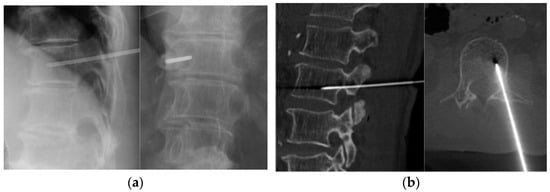

Finally, 117 patients (mean age of 62.5 years; 73 males) were included in this retrospective study (Table 1). All biopsies were performed under image guidance with local anesthesia. Thoracic, lumbar, and larger lesions were assessed under fluoroscopy (73 cases), whereas cervical, sacral, and smaller lesions were assessed under CT guidance (44 cases) (Figure 1). The most common vertebral level was the lumbar spine in 57 patients (48.7%), followed by the thoracic spine in 37 (31.6%), sacral spine in 16 (13.7%), and cervical spine in 7 patients (6.0%).

Figure 1. Image-guided percutaneous needle biopsy. (a) Fluoroscopic biopsy. (b) CT-guided biopsy.